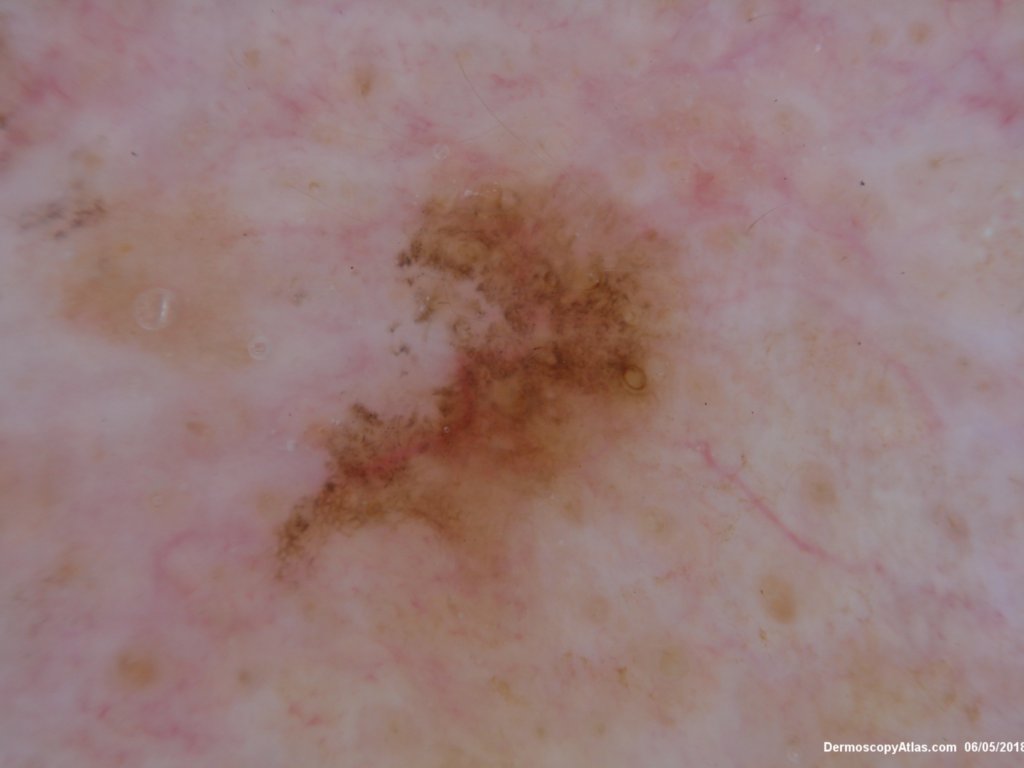

Site: Neck side

Diagnosis: Pigmented Intraepidermal carcinoma

Type: Dermlite Polarised

Submitted By: Ian McColl

Some pigmented lesions look melanocytic, However this is a pigmented intraepidermal carcinoma. Some areas show more full thickness atypia than others. The dermatoscopy shows some dots in rows but there are other grey dots showing regression at one edge.